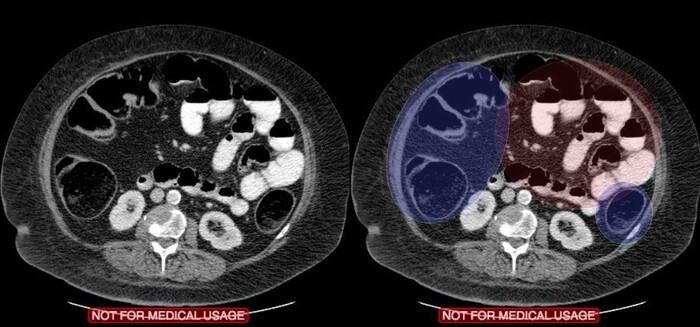

Сделали компьютерную томографию почти всего тела по протоколу множественной травмы (голова, шея, органы грудной клетки + органы брюшной полости включая позвоночник и таз).

Здесь прилагаю только КТ головы, на котором особых патологических изменеий выявлено не было: